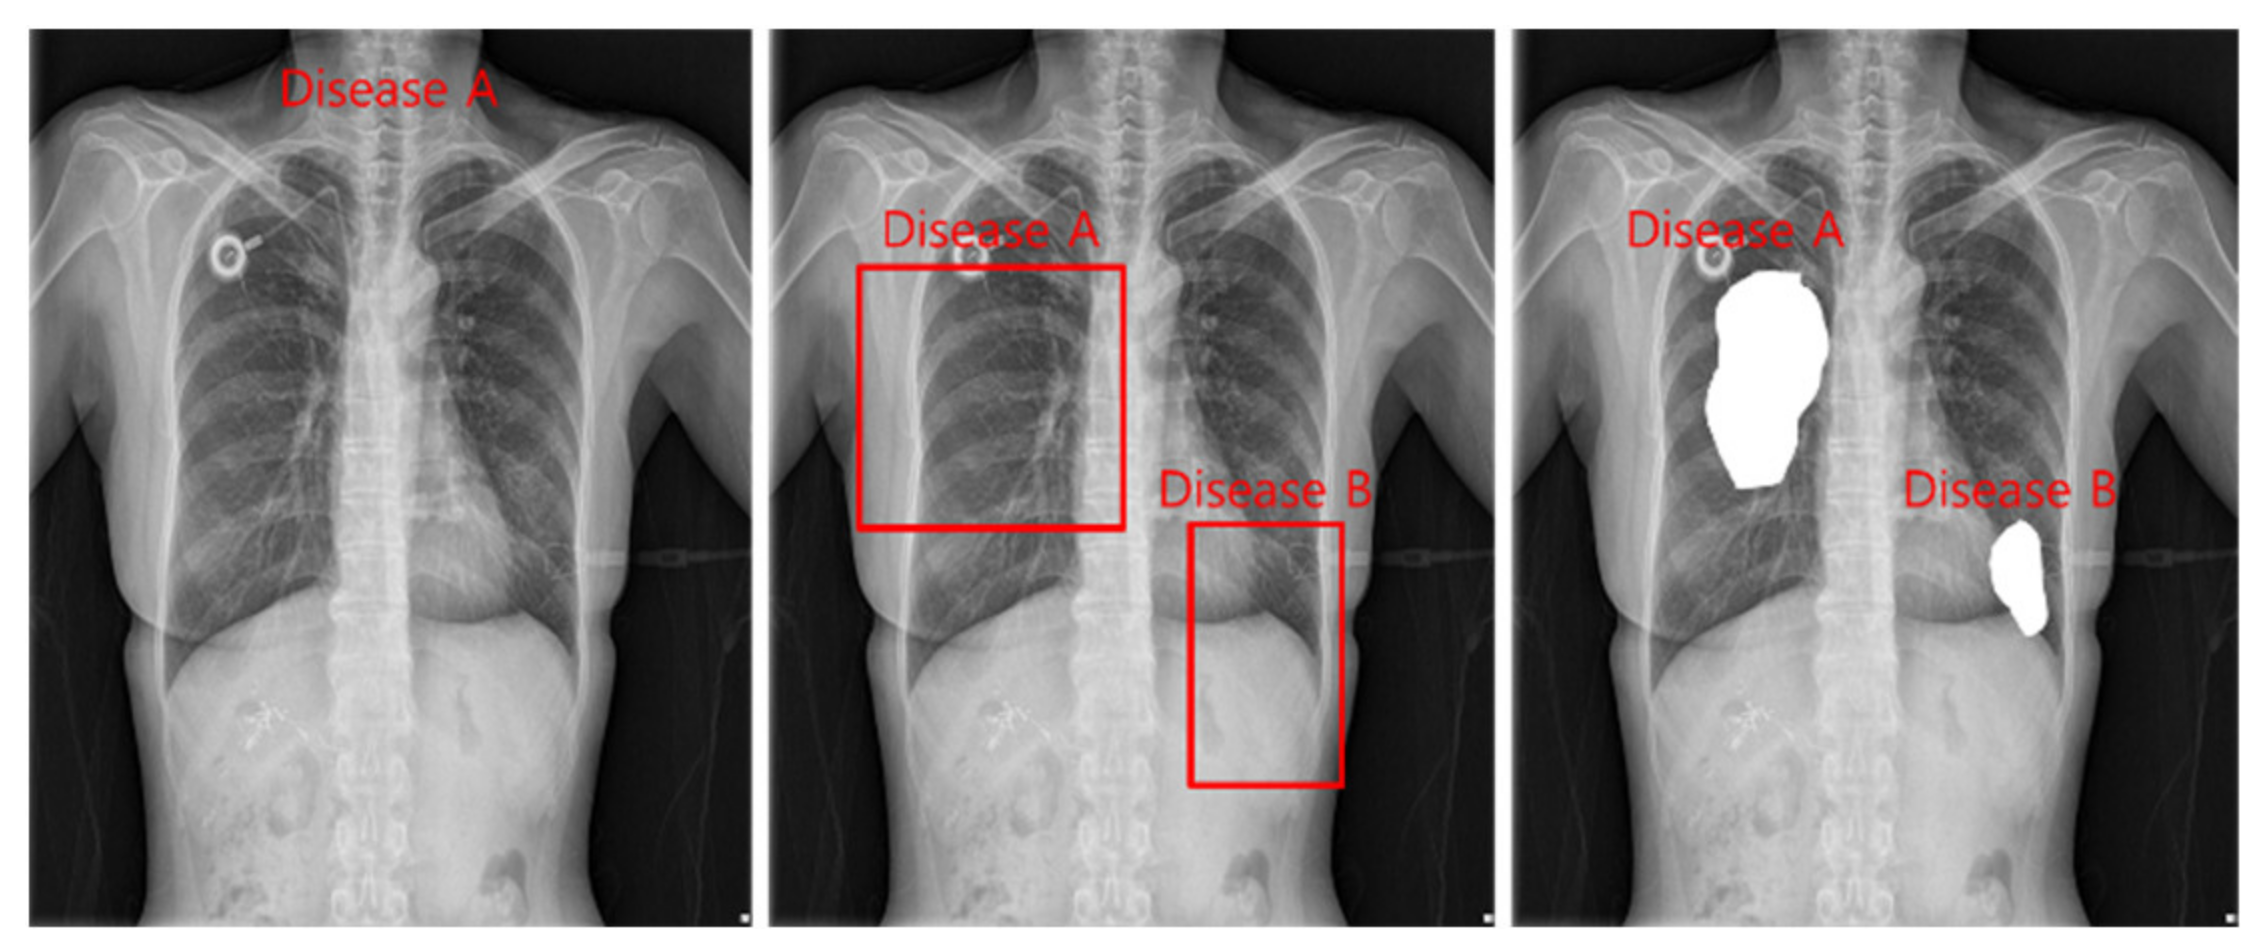

The tasks of deep learning currently utilized in health care are divided into classification, detection, and segmentation, as shown in Figure 2. Models used in all tasks utilize heavy and accurate SOTA models due to the nature of the medical field requiring refinement.

Classification is a task that divides negatives and positives by learning images and labels of diseases and is a method that focuses on learning for inferring disease names. For detection, a Bounding Box is marked around the location of a disease, and the disease name and Bounding Box coordinates are learned to infer the location information of the disease. Segmentation is a method of inferring the disease pixel by pixel by learning the location pixel of the disease.

Figure 2. Classification, detection, and segmentation task.